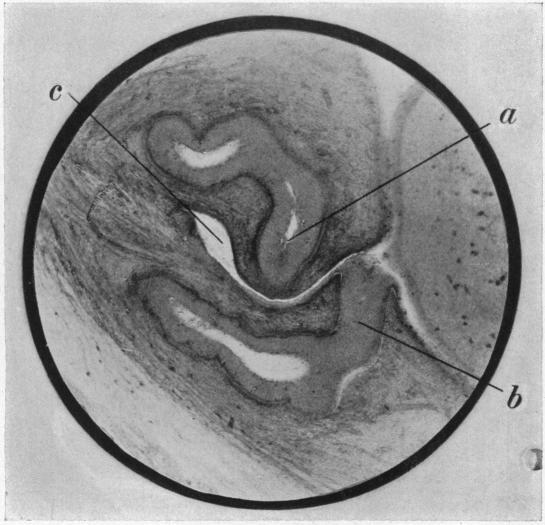

II. Variations in the Anatomy of the Nasolachrymal Passages.

Ann Surg. 1911 Aug;54(2):148-52. doi: 10.1097/00000658-191108000-00002.